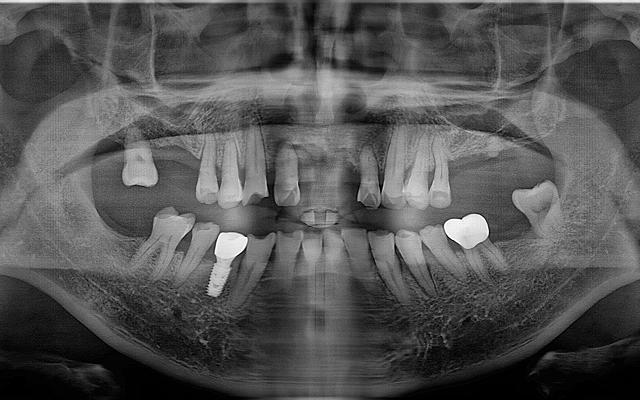

전악 케이스

- 상·하악 전체 보철 설계를 통해 정확한 교합(물림) 회복

- 심미·발음·저작 기능을 종합 고려한 자연스러운 전악 임플란트